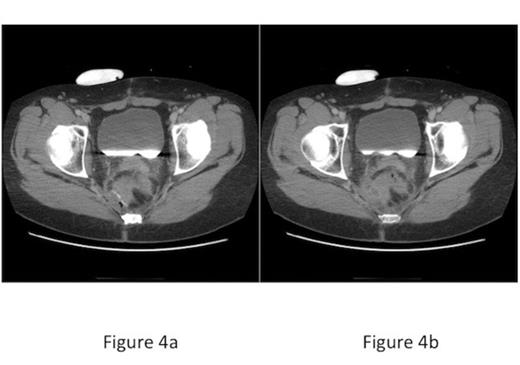

After completing chemotherapy, the anastomosis was evaluated with gastrograffin enema, which showed a normal anastomosis and no leak (Figure 2). After the enema, the patient experienced rectal pain and fever. Rectal exam revealed a patent anastomosis with mild right-sided tenderness. Flexible sigmoidoscopy revealed a well-healed circular EEA anastomosis. The linear staple line revealed a 3 mm defect (Figure 3). Contrast CT scan of the abdomen and pelvis demonstrated a 2 cm fluid collection along the linear staple line with small amount of free air in adjacent mesenteric fat (Figure 4). Two-week of antibiotics facilitated symptom resolution. Follow-up CT scan documented resolution of the abscess and air.

CT scan of abdomen/pelvis a) Small amount of free air adjacent to linear staple line, b) Abscess adjacent to linear staple line